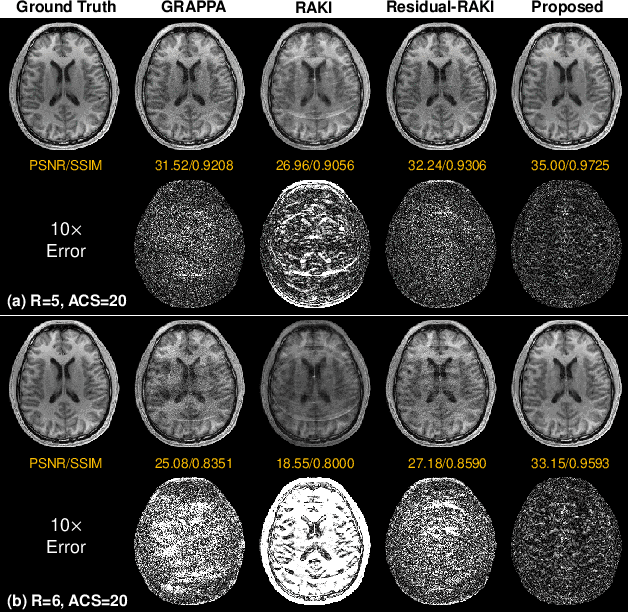

Abstract:Parallel imaging is a commonly used technique to accelerate magnetic resonance imaging (MRI) data acquisition. Mathematically, parallel MRI reconstruction can be formulated as an inverse problem relating the sparsely sampled k-space measurements to the desired MRI image. Despite the success of many existing reconstruction algorithms, it remains a challenge to reliably reconstruct a high-quality image from highly reduced k-space measurements. Recently, implicit neural representation has emerged as a powerful paradigm to exploit the internal information and the physics of partially acquired data to generate the desired object. In this study, we introduced IMJENSE, a scan-specific implicit neural representation-based method for improving parallel MRI reconstruction. Specifically, the underlying MRI image and coil sensitivities were modeled as continuous functions of spatial coordinates, parameterized by neural networks and polynomials, respectively. The weights in the networks and coefficients in the polynomials were simultaneously learned directly from sparsely acquired k-space measurements, without fully sampled ground truth data for training. Benefiting from the powerful continuous representation and joint estimation of the MRI image and coil sensitivities, IMJENSE outperforms conventional image or k-space domain reconstruction algorithms. With extremely limited calibration data, IMJENSE is more stable than supervised calibrationless and calibration-based deep-learning methods. Results show that IMJENSE robustly reconstructs the images acquired at 5$\mathbf{\times}$ and 6$\mathbf{\times}$ accelerations with only 4 or 8 calibration lines in 2D Cartesian acquisitions, corresponding to 22.0% and 19.5% undersampling rates. The high-quality results and scanning specificity make the proposed method hold the potential for further accelerating the data acquisition of parallel MRI.

Abstract:Parallel imaging is a widely-used technique to accelerate magnetic resonance imaging (MRI). However, current methods still perform poorly in reconstructing artifact-free MRI images from highly undersampled k-space data. Recently, implicit neural representation (INR) has emerged as a new deep learning paradigm for learning the internal continuity of an object. In this study, we adopted INR to parallel MRI reconstruction. The MRI image was modeled as a continuous function of spatial coordinates. This function was parameterized by a neural network and learned directly from the measured k-space itself without additional fully sampled high-quality training data. Benefitting from the powerful continuous representations provided by INR, the proposed method outperforms existing methods by suppressing the aliasing artifacts and noise, especially at higher acceleration rates and smaller sizes of the auto-calibration signals. The high-quality results and scanning specificity make the proposed method hold the potential for further accelerating the data acquisition of parallel MRI.